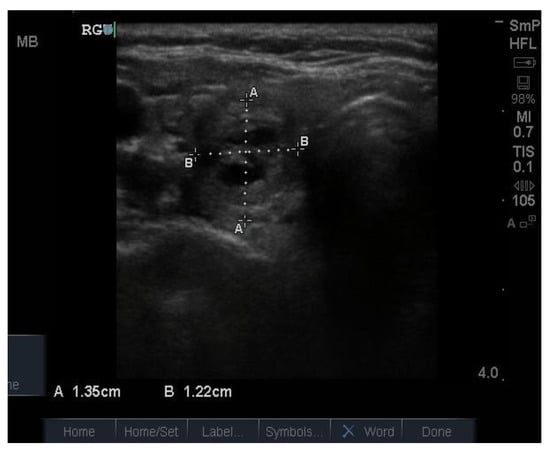

Follicular nodules are much less common than colloid nodules with a different appearance on ultrasound; they are more cellular, giving a solid appearance, with a whitish colour, i.e., less hypoechoic. They too have a sharp edge and halo and grow slowly over time []. The problem with these lesions is that FNAB is unable to differentiate between a benign follicular adenoma and follicular cancer, and if the latter is suspected, thyroid surgery is the final arbitrator. About 10% of benign thyroid nodules are follicular, and most of them end up being removed. Two examples of follicular nodules that were finally proven to be benign are shown in Figure 4. On follow-up ultrasound (US), 6–12 months later, repeat biopsy might be indicated if a nodule has grown by 20% or more in two or more dimensions; benign nodules also grow, but less quickly.

Figure 4.

Two examples of follicular nodules that were shown at surgery to be benign. The nodules are roughly oval shaped, slightly hyper echoic and have sharp edges and, particularly, the bigger of the two, thick halos.